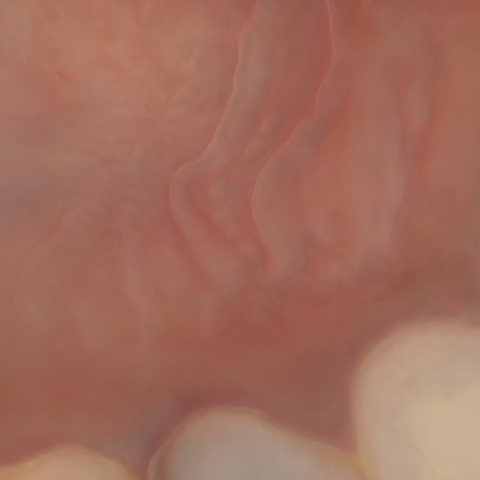

Image 734 / 1103

NHD39174

Annotated as "Good"

Original Image Rendering Image